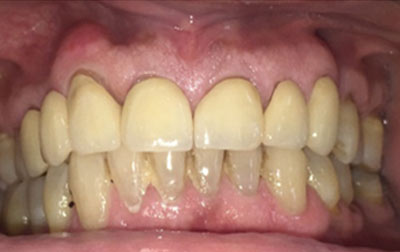

Smile makeover:

Radiating confidence through a beaming smile can truly uplift your spirits. A captivating smile holds significant sway in social and professional spheres, enhancing your overall appeal. However, numerous individuals refrain from revealing their teeth in public or photographs due to personal dissatisfaction. If you find yourself in this category, why not consider allowing us to assist you in attaining the smile you've always envisioned? Embark on a journey toward your ideal smile with our transformative smile makeover. A smile makeover transcends the mere resolution of dental issues as they arise. It constitutes a holistic plan to rejuvenate your smile, intricately tailored to complement your distinct facial features and aesthetic inclinations. The outcomes are nothing short of remarkable—both in terms of your visual transformation and the surge of newfound confidence you'll experience.